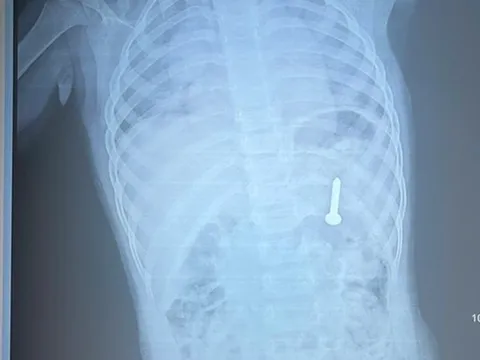

Tình trạng H. ho nặng hơn mới được đưa đi khám. Kết quả chụp cắt lớp vi tính tại bệnh viện địa phương phát hiện dị vật ở phế quản phải của bệnh nhân, sau đó trẻ được chuyển lên Bệnh viện Nhi Trung ương.

Tại Trung tâm Hô hấp, bệnh nhi được chỉ định nội soi phế quản để gắp dị vật. Quá trình can thiệp gặp nhiều khó khăn do dị vật đã tồn tại lâu ngày, bị bao bọc bởi tổ chức viêm và mô hạt. Các bác sĩ phải phối hợp nội soi ống cứng với laser để cắt bỏ tổ chức xung quanh và lấy ra dị vật là hạt hồng xiêm kích thước khoảng 1×3cm.